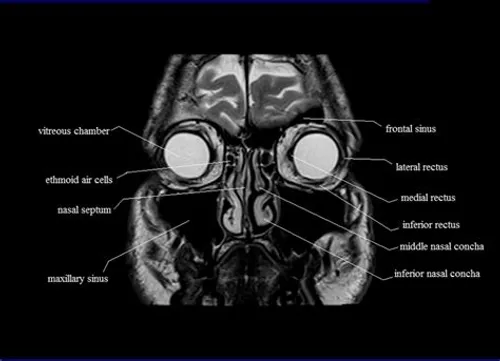

A paranasal sinuses (PNS) MRI generates an image of the four pairs of air-filled gaps that surround the nasal cavity, pituitary gland, and soft tissues.

A magnetic resonance imaging (MRI) PNS (paranasal sinus) creates pictures of the sinuses. Sinuses are the air filled spaces present around the nasal cavity, pituitary gland and soft tissues.

PNS in MRI stands for para nasal sinuses. A  PNS MRI scan uses radio waves and strong magnets to create a magnetic field that helps in producing detailed scan images of the para nasal sinuses.

Normal paranasal sinuses MRI images show 4 paired air-filled spaces with no evidence of damage infection or diseases.

The paranasal sinuses usually are 4 pairs.